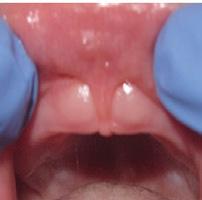

There Is Only One Smile That Matters. Yours!

You are in good hands! Dr. Makarita is the only accredited Fellow of the American Academy of Cosmetic Dentistry in Virginia.

BEFORE AFTER

At Tysons Aesthetic Dentistry Dr. Makarita has designed and equipped his practice with your smile in mind. Dedicated care and attention are just the beginning.

As a general dentist with a passion for aesthetic and cosmetic dentistry, whether a simple filling or a smile makeover, Dr. Makarita’s priority is to help you love your smile.

Since earning his doctorate from the Medical College of Virginia, Dr. Makarita has continually upgraded his skills and knowledge with continuing education so he can always bring you the most advanced options for all your dental needs.

Always welcoming new patients! Call 703-532-2020  8150 Leesburg Pike | Suite 503, Vienna VA 22182 www.ilovethatsmile.com

FREE SMILE EVALUATION In person or visit website for virtual smile consultation

Dr. H.R. Makarita

Accredited Fellow, American Academy of Cosmetic Dentistry

Master, Academy of General Dentistry

Master, International Congress of Oral Implantologists

Master, Las Vegas Institute for Advanced Dental Studies

to Love Your Smile? Dr. Makarita would love to meet you! About